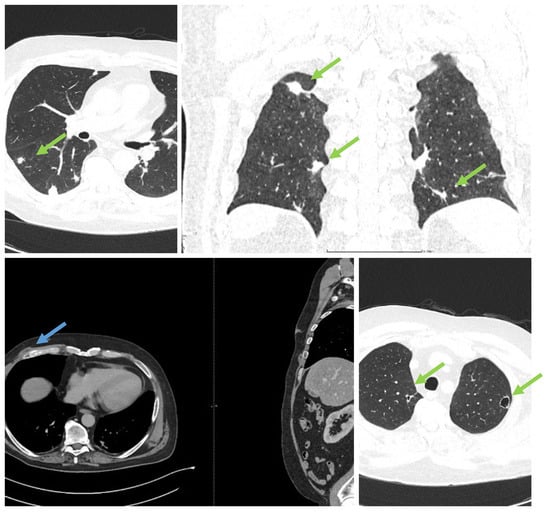

It was suspected that there was a metastatic tumor, and a full-body CT scan was performed (Figure 2). The CT scan discovered multiple abscesses in the lungs and under the skin. A second contrast MRI (Figure 3) scan was conducted which revealed abscesses in all parts of the brain, including the right thalamus and left cerebellar hemisphere, with ring-like contrast-enhancing lesions. However, the lesions were relatively stable compared to the previous MRI.

The subsequent clinical course after meropenem was stopped when it was relatively severe, with the patient developing intense right eye pain and a sudden drop in visual acuity, which required a step-up of pain medication; eventually, the patient received a combination of metamizole, tramadol, acetaminophen, pethidine, and nefopam. Even so, the patient declared a 10/10 Borg RPE pain score. The second MRI showed right posterior eye pole thickening and retroorbital edema, highly suspicious retinal detachment, which the ophthalmology consult confirmed as no light perception, so the decision was made to re-administer meropenem, again with a decrease in the pain scale. Also, there was a spike in CRP level that corroborated with the withdrawal of meropenem and improvement with its re-administration (Figure 5). After re-administration of meropenem, the clinical course dramatically improved, and the patient received only on-demand acetaminophen.

Figure 3. MRI. (Ring-enhancing lesions are present in all cerebral lobes and the thalamus. Different sequences showing brain abscesses are indicated by green arrows; the star indicates eye involvement).